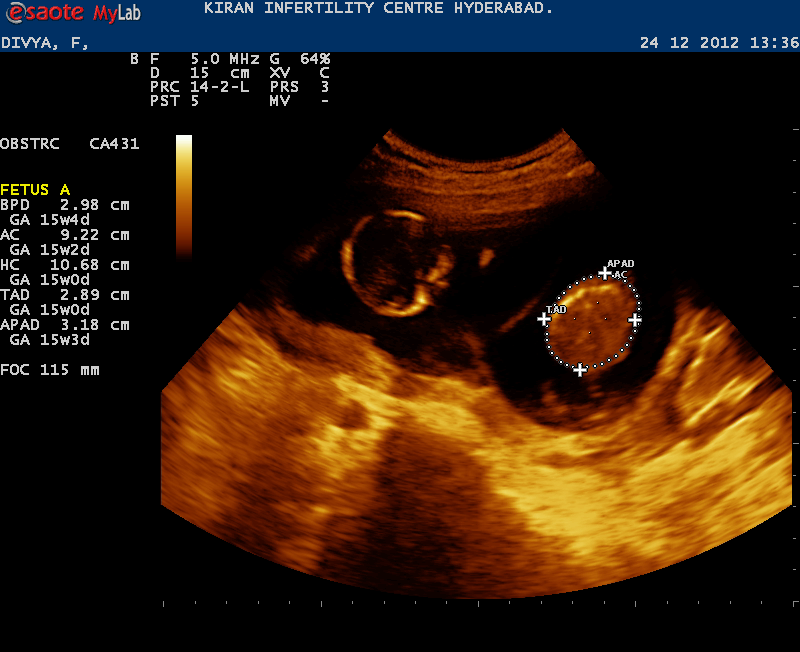

December 25, 2012 - 14 week update from Anjani.

Fetus A

GA :15w1d

BIPARIETAL DIAMETER : 2.98cm

HEAD CIRCUMFERENCE : 10.68cm

ABDOMINAL CIRCUMF : 9.22cm

FEMUR LENGTH : 1.69cm

TRANSV ABD DIAM : 2.89cm

ANT-POST ABD DIAM : 3.18cm

ESTIM FETAL WEIGHT : 114g

Heart Rate130-150BPM

Fetus B

GA :15w0d

BIPARIETAL DIAMETER : 2.77cm

HEAD CIRCUMFERENCE : 10.88cm